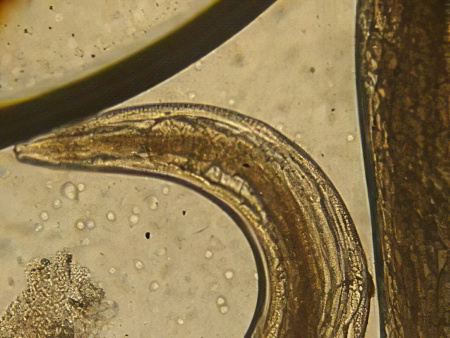

Микрофотографии яиц гельминтов Toxocara canis

Раздел: Фотоэссе